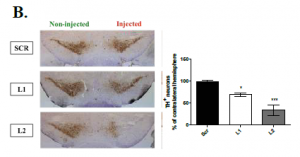

Τίτλος Ερευνητικού Έργου: GPER1 μεμβρανικός υποδοχέας των νευρο-οιστρογόνων: ένας νέος ψυχοφαρμακολογικός στόχος με υποσχόμενη ταχεία δράση

Επιστημονική Υπεύθυνη: Δάλλα Χριστίνα